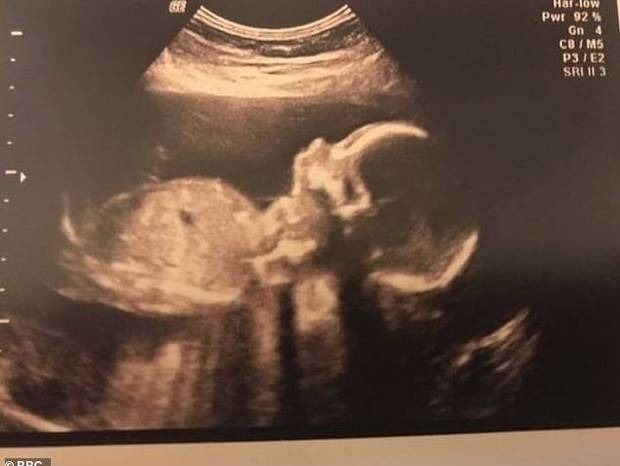

Segundo o registro da Polícia Militar, a mãe da bebê, de 34 anos, foi internada em 24 de abril, com 28 semanas de gestação. Devido a uma alteração na pressão arterial, os médicos optaram por induzir o parto.

Na madrugada do dia 1º de maio, a mulher entrou em trabalho de parto. Em certo momento, a obstetra convidou o pai da criança, que acompanhava tudo, para observar de perto.

O pai chegou a ver a filha piscando e mexendo a boca.